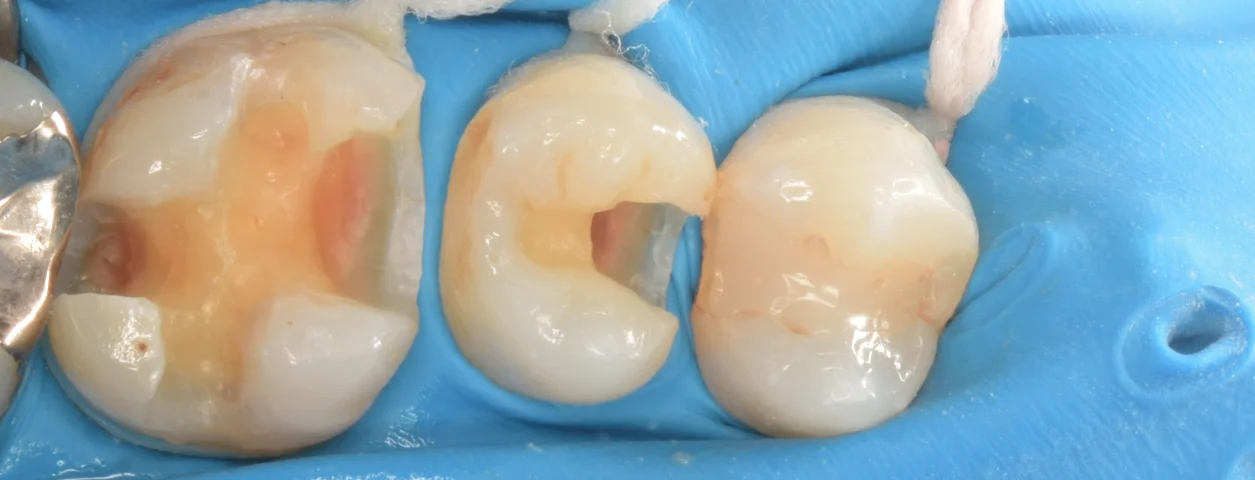

虫歯を除去し切ったのがこちらになります。

自費の治療ですし、つけられそうだったので、ラバーダム防湿というゴムのマスクを装着しています。

保険点数を割り当てられていないため、私は保険のCRではラバーダム防湿は行いませんので、これは自費のみの処置となります。

事故的に唾液で汚染されたり、湿気を落とすことができるので、ダイレクトボンディングにとっては有利に働きます。

若干シワがありますが・・・漏れてる様子はないので、特に問題はありません。